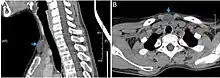

Epidermoid cysts are usually diagnosed when a person notices a bump on their skin and seeks medical attention. The definitive diagnosis is made after excision by a pathologist based on microscopic appearance of a cystic lesion lined by cornified epithelium containing lamellated keratin without calcifications. They can also be seen as isointense lesions on MRI or hyperintensities on FLAIR.

CT scan, showing a homogenous hypodense volume (unspecific cyst-like)

Histopathology, showing a keratinizing stratified squamous epithelium, and a lumen containing keratin flakes

Histopathology showing epithelium and lamellated keratin (left)